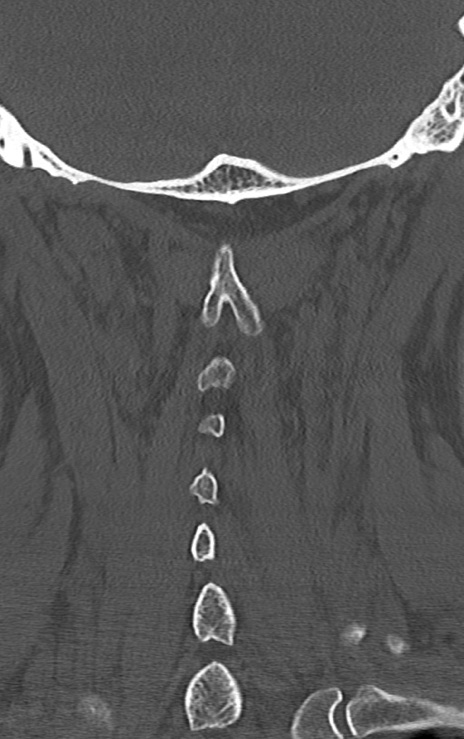

頚椎CT

矢状断像